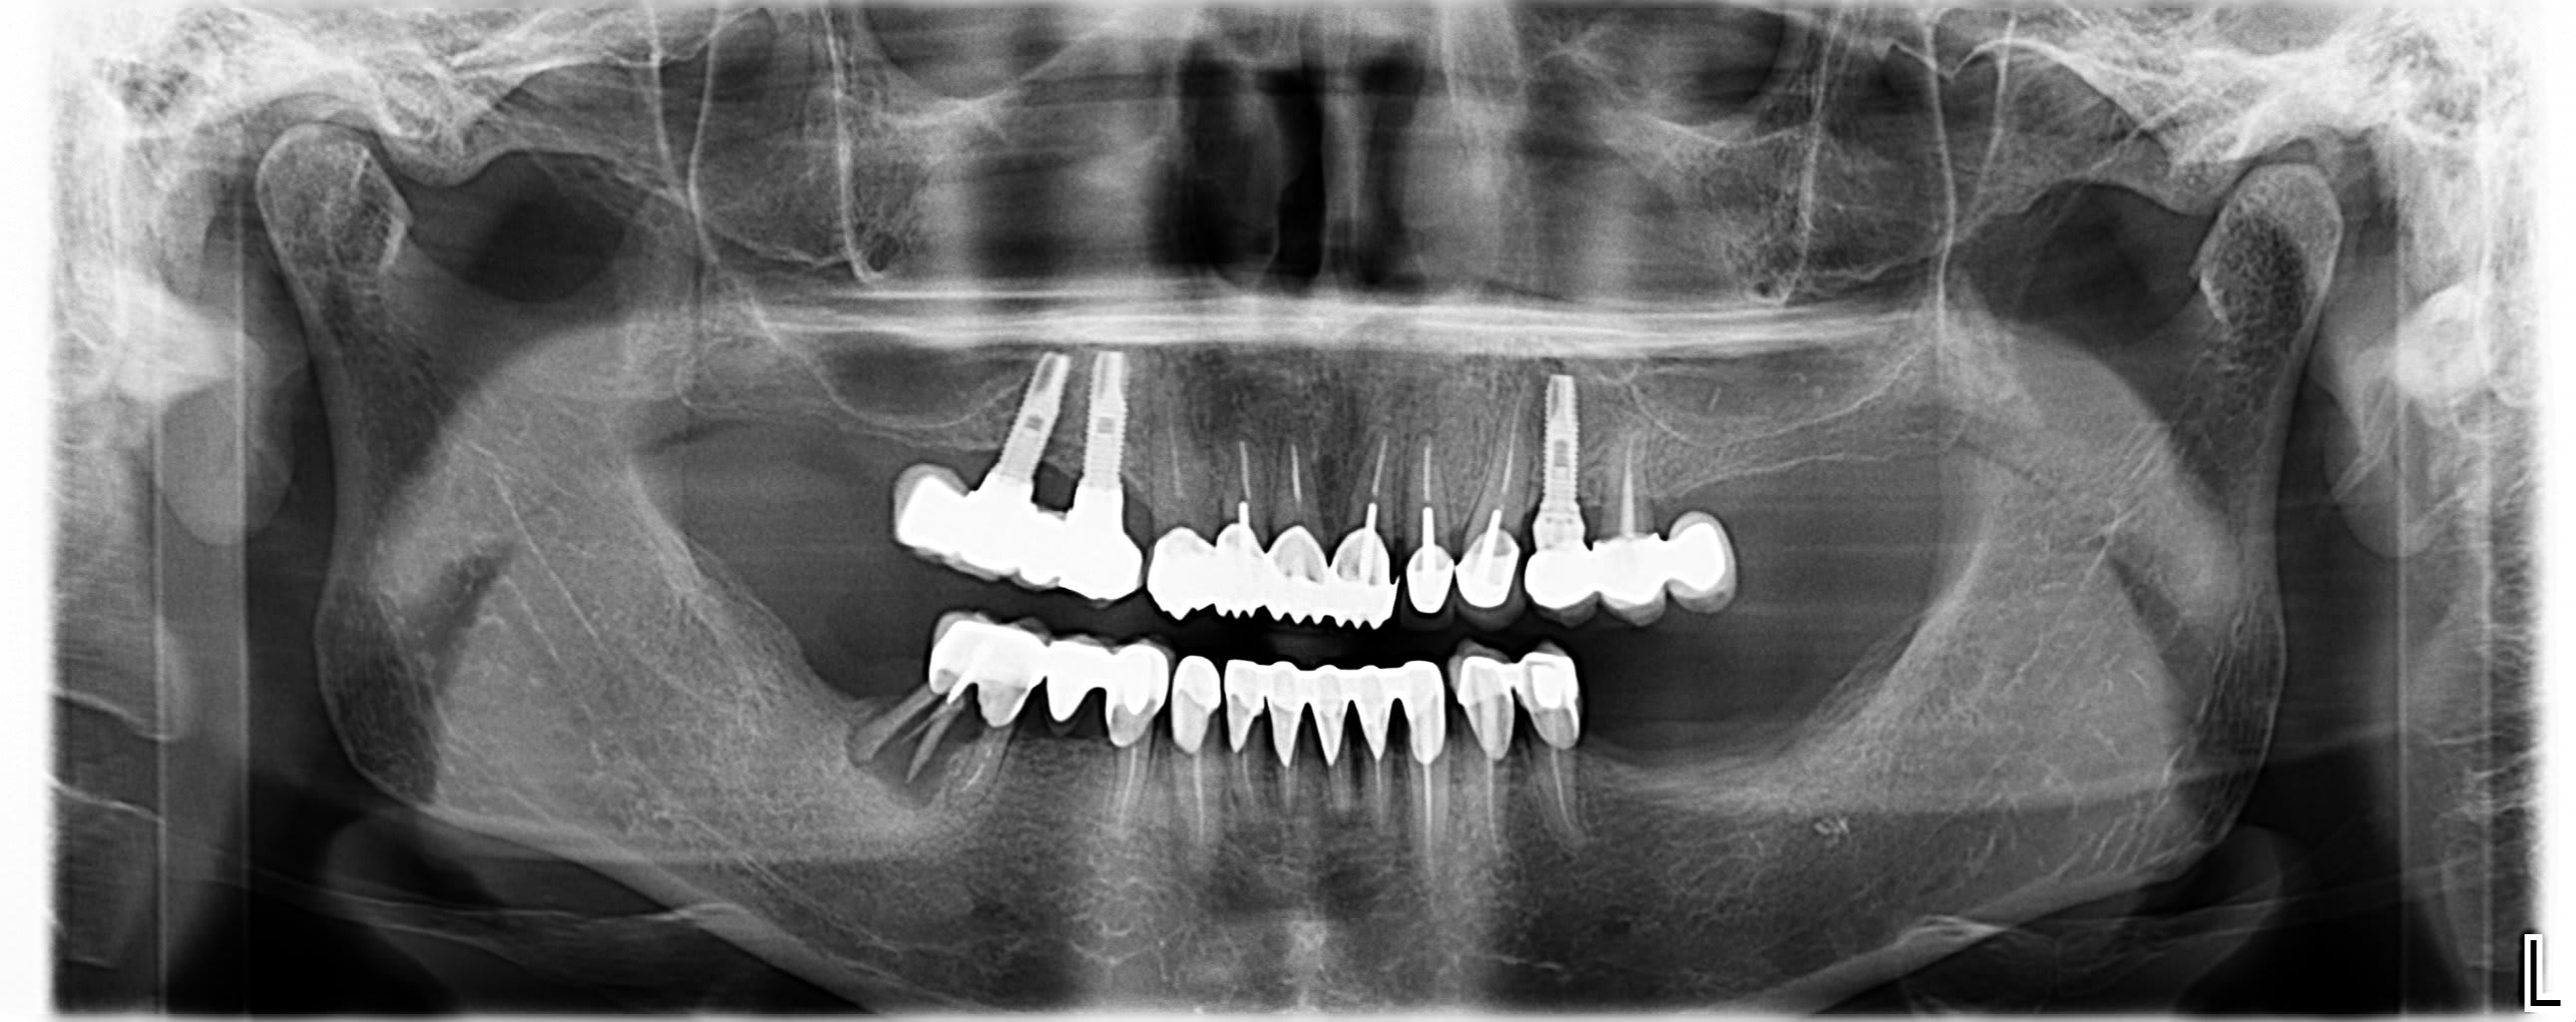

Bonsoir

Pouvez vous m'aider a identifier ces implants. La seule chose que je sais, c'est que ce n'est pas tout jeune !

Merci

Photo pluton1b h9n4ea - Eugenol

Faudrait démonter pour être certain…..parce que j’arrive pas à voir la connexion…

En 1 je dirais du Sterioss

https://www.spotimplant.com/fr/implants-dentaire/steri-oss/steri-oss-original-non-hex

En 2, des 3M ESPE

https://www.spotimplant.com/fr/implants-dentaire/espe-3m/fixture

Pranou

11/06/2024 à 13h55

Merci Pluton, je vais déposer la prothèse pour essayer d'avoir plus d'informations